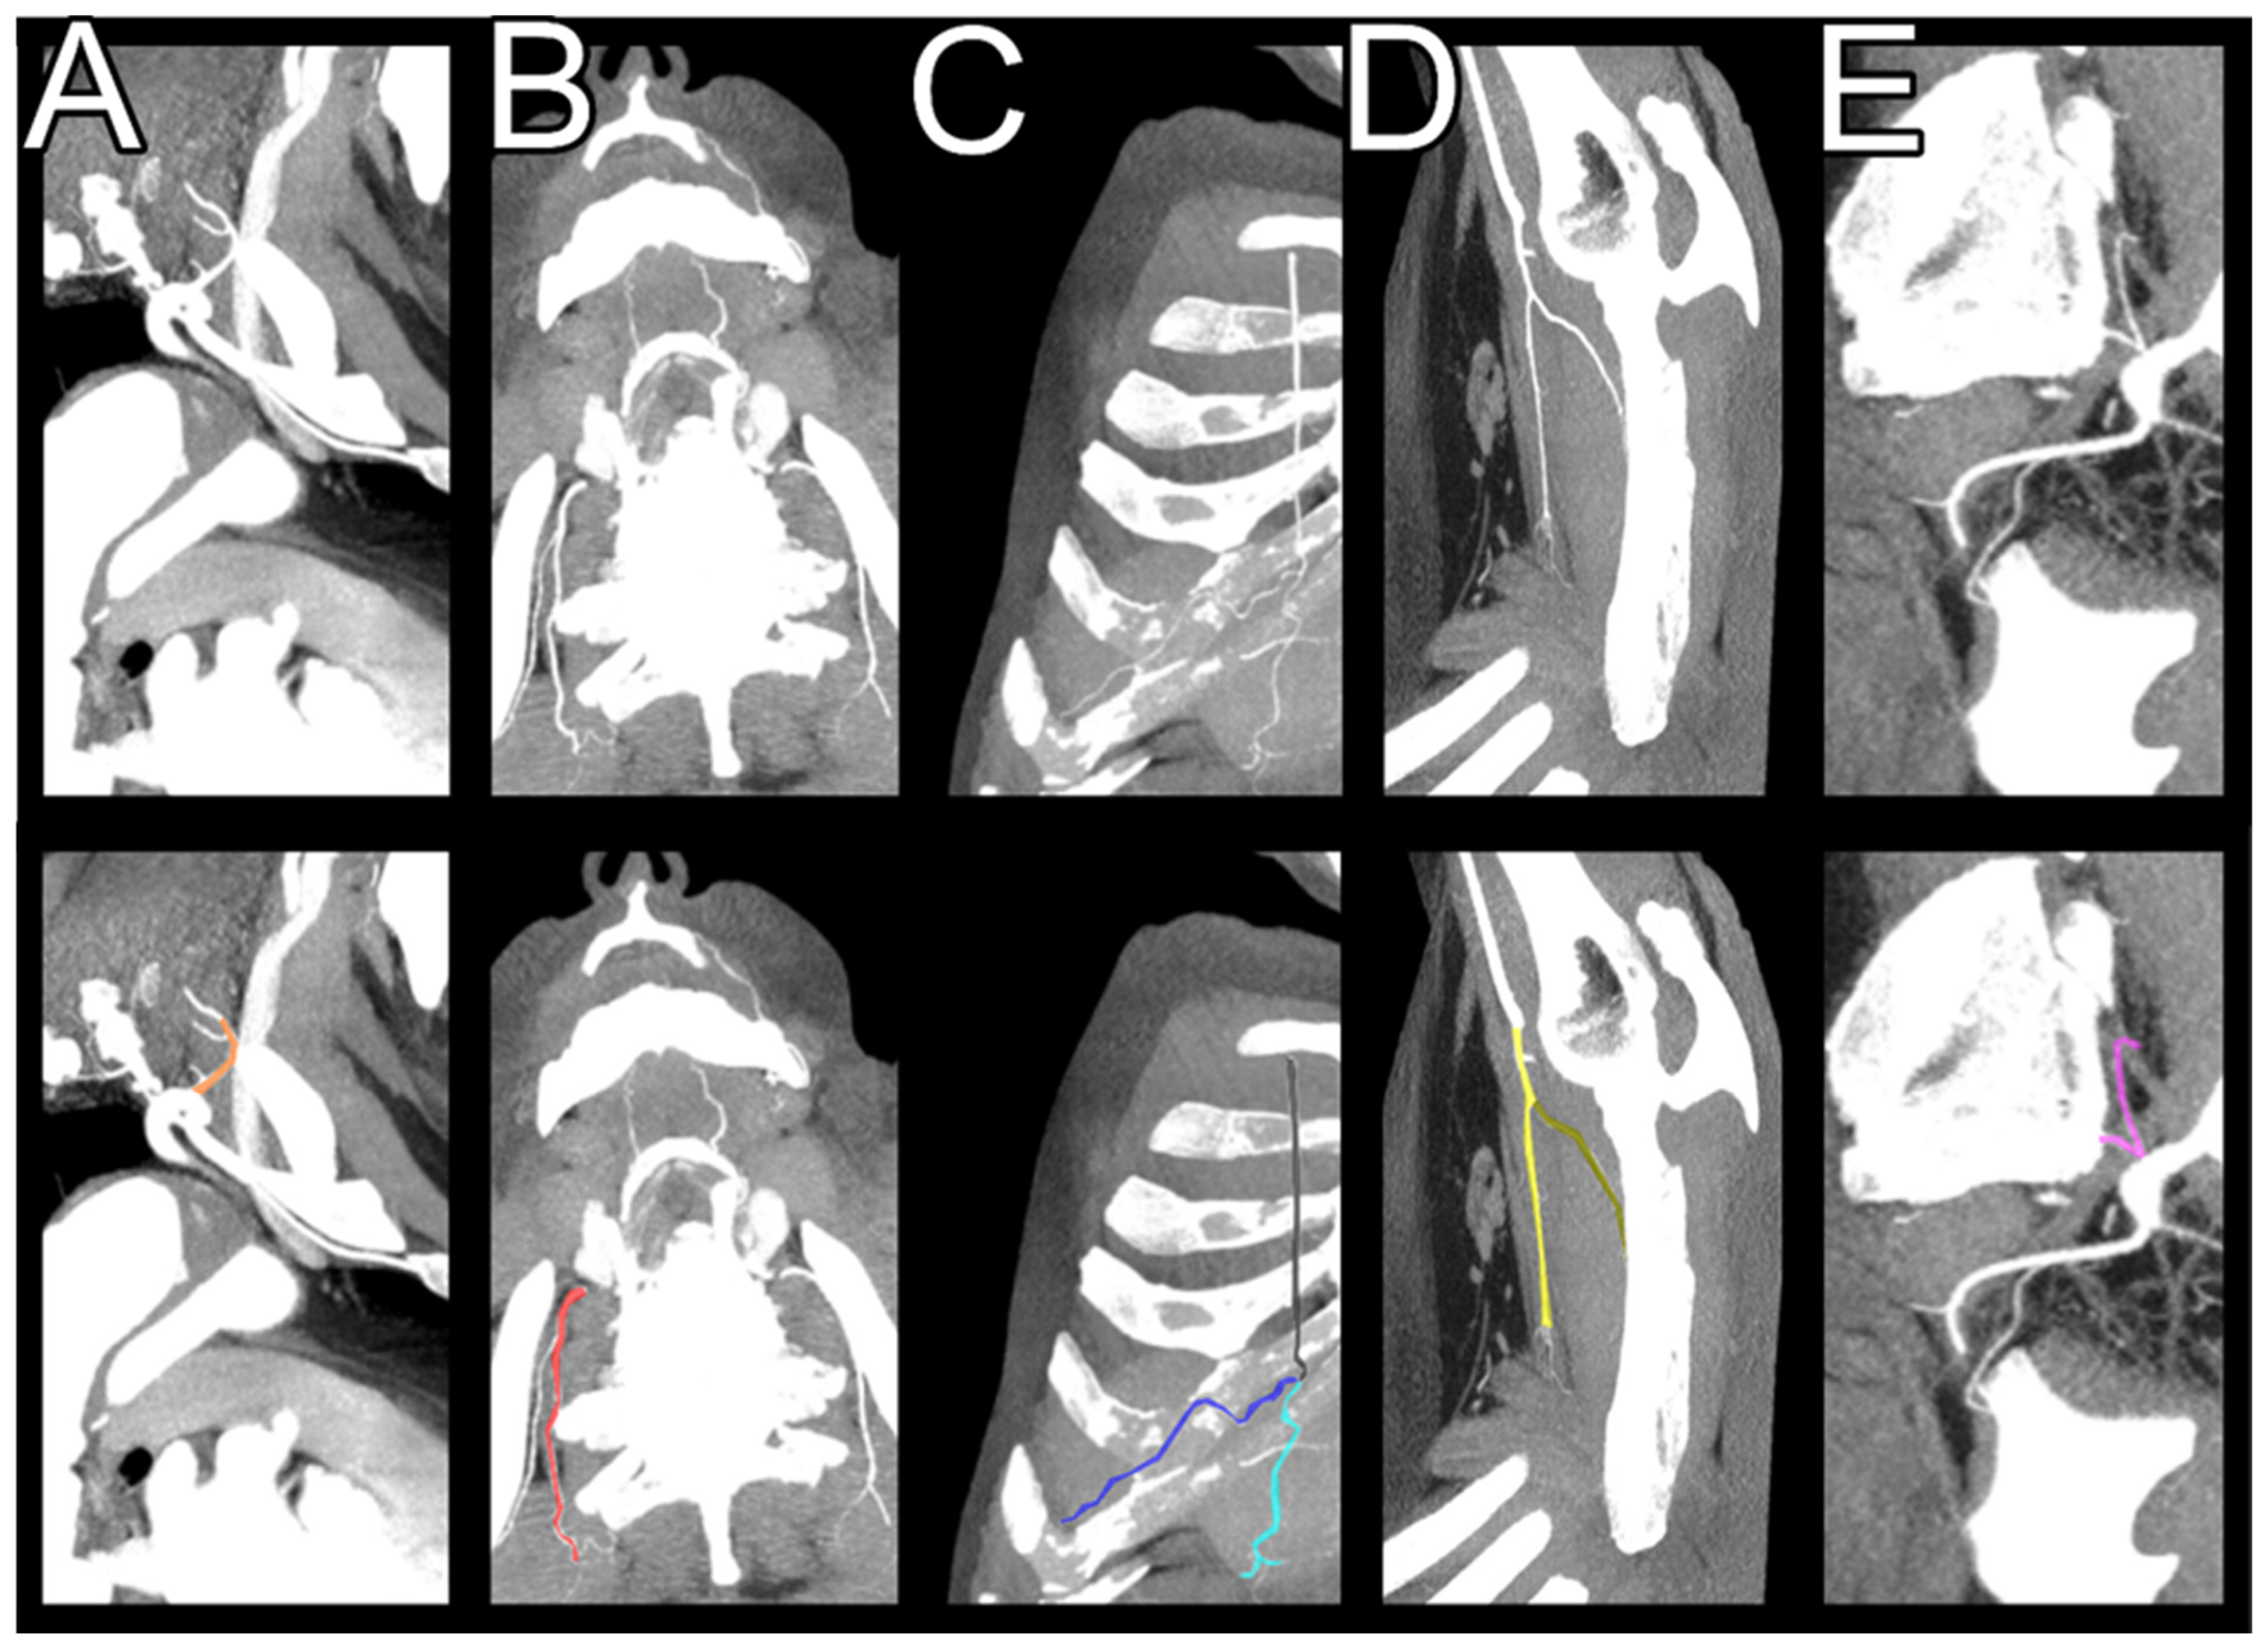

2.2. Imaging Characteristics and Analysis

2.3. Visualizations and Measurements